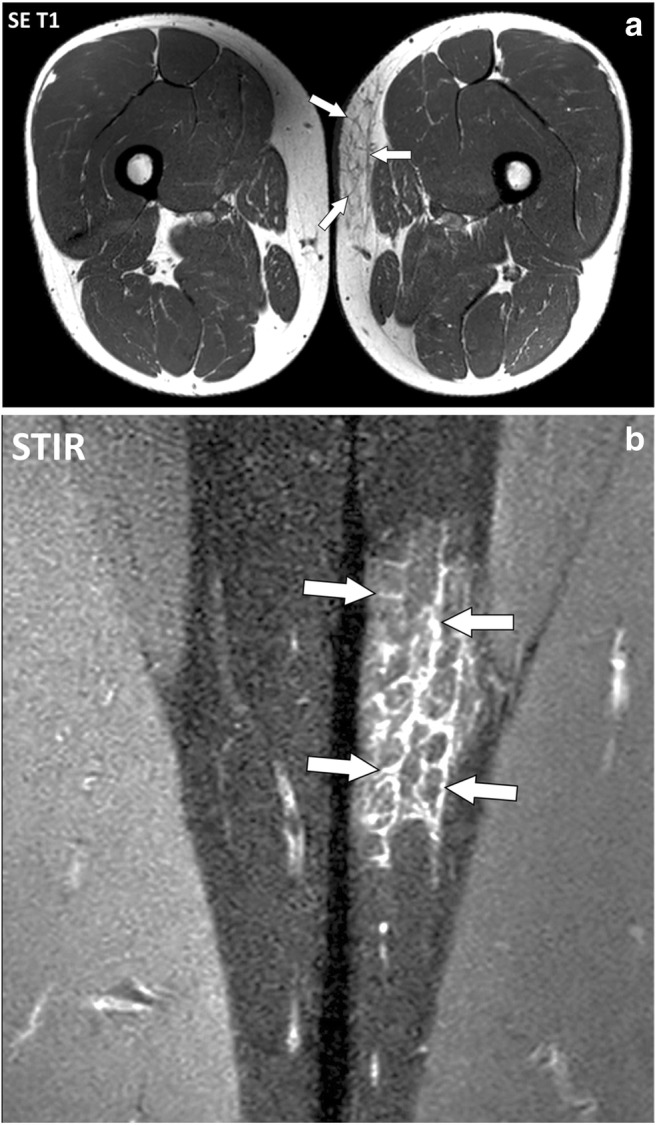

Fig. 9.

a Axial SE T1-weighted and (b) close-up coronal STIR images of the thighs of a 43-year-old male with dermatomyositis. The fascia superficialis of the left thigh (arrows) is thickened with fluid signal intensity

Fig. 15.

a Axial and (b) coronal STIR images of the thighs of a 16-year-old female with dermatomyositis and anti-TIF1-γ antibodies. MRI demonstrates bilateral symmetrical involvement of the muscles mostly in the quadriceps and gracilis muscles. Blood level of creatine phosphokinase (CPK) was normal. At MRI, involved muscles are heterogenous with a “salt and pepper” pattern in the axial plane (arrowheads) while they maintain a fibrillar organization with fluid signal intensity (white arrows) and low signal intensity (black arrows) striations in the coronal plane